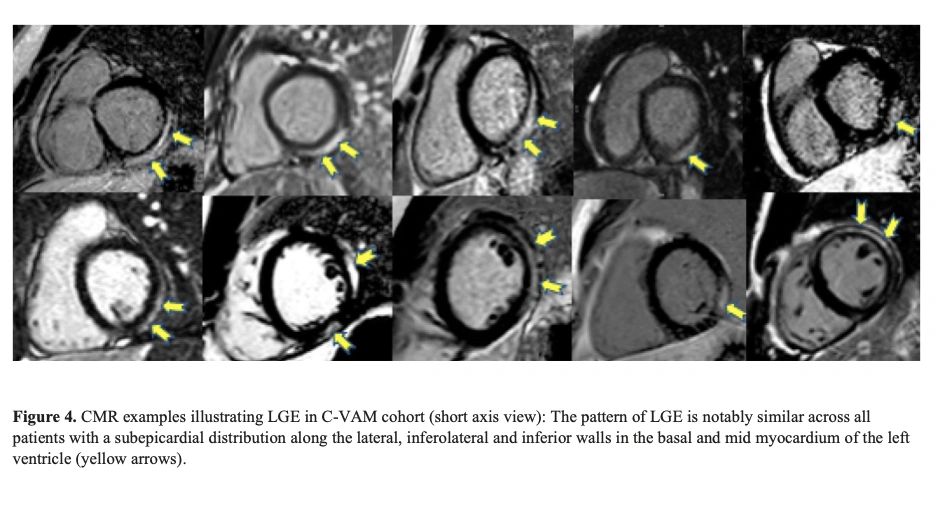

Notably, a retrospective multi-centre study across 16 US hospitals including patients <21 years of age with a diagnosis of myocarditis following COVID-19 vaccination, found concerning abnormalities in heart tissue (the left ventricle) (See image with yellow arrows).

Jain SS, et al doi: 10.1542/peds.2021-053427.

Careful monitoring is required to see if these abnormalities lead to fibrosis, which can have long-term implications for young patients.